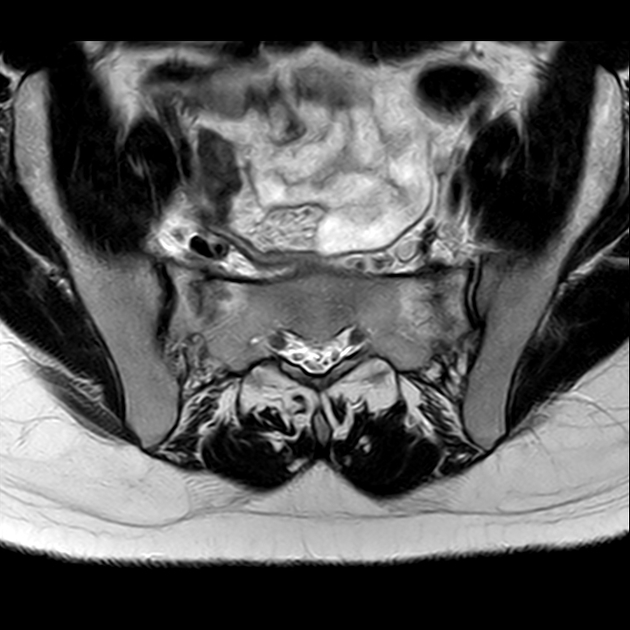

磁共振检查:

T2